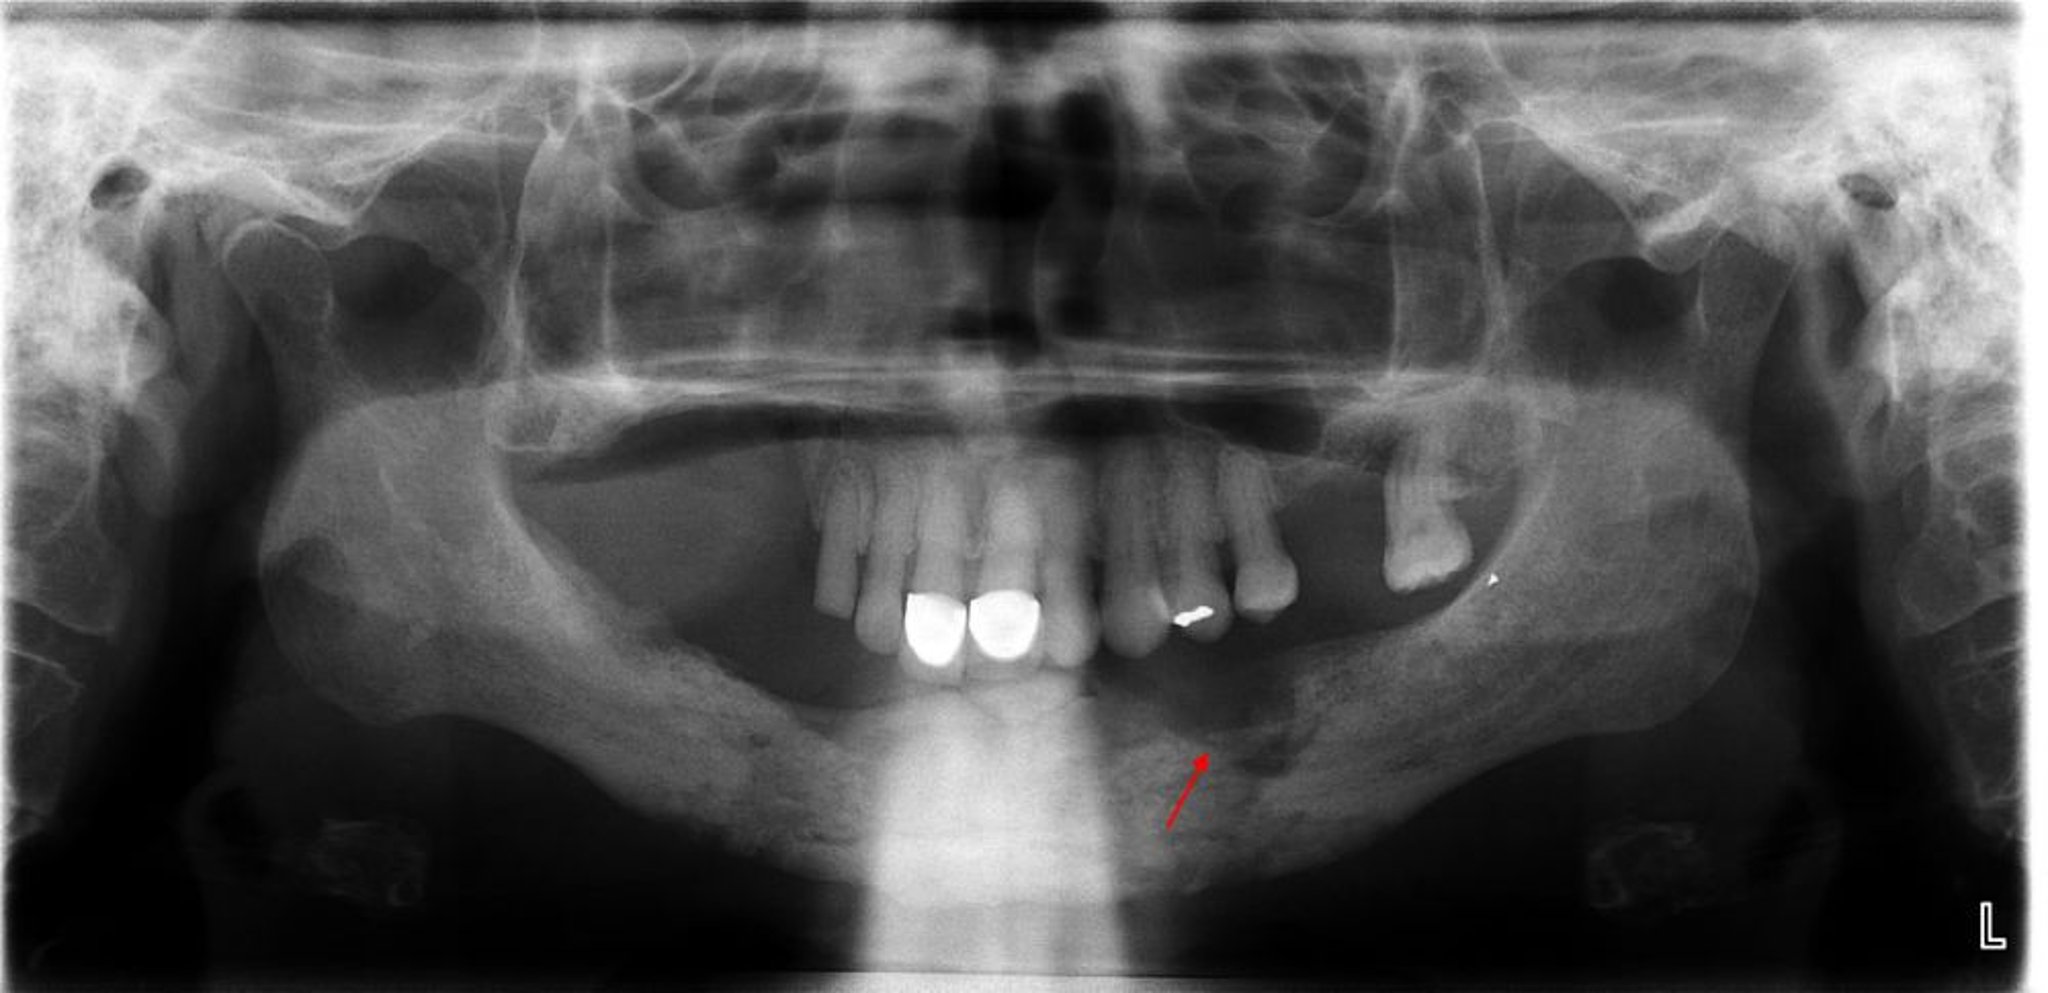

This radiograph reveals osteomyelitis with an evident sequestrum (nonviable bone) noted in the left mandibular quadrant (arrow).

Image courtesy of Byron (Pete) Benson, DDS, MS, Texas A&M University Baylor College of Dentistry.